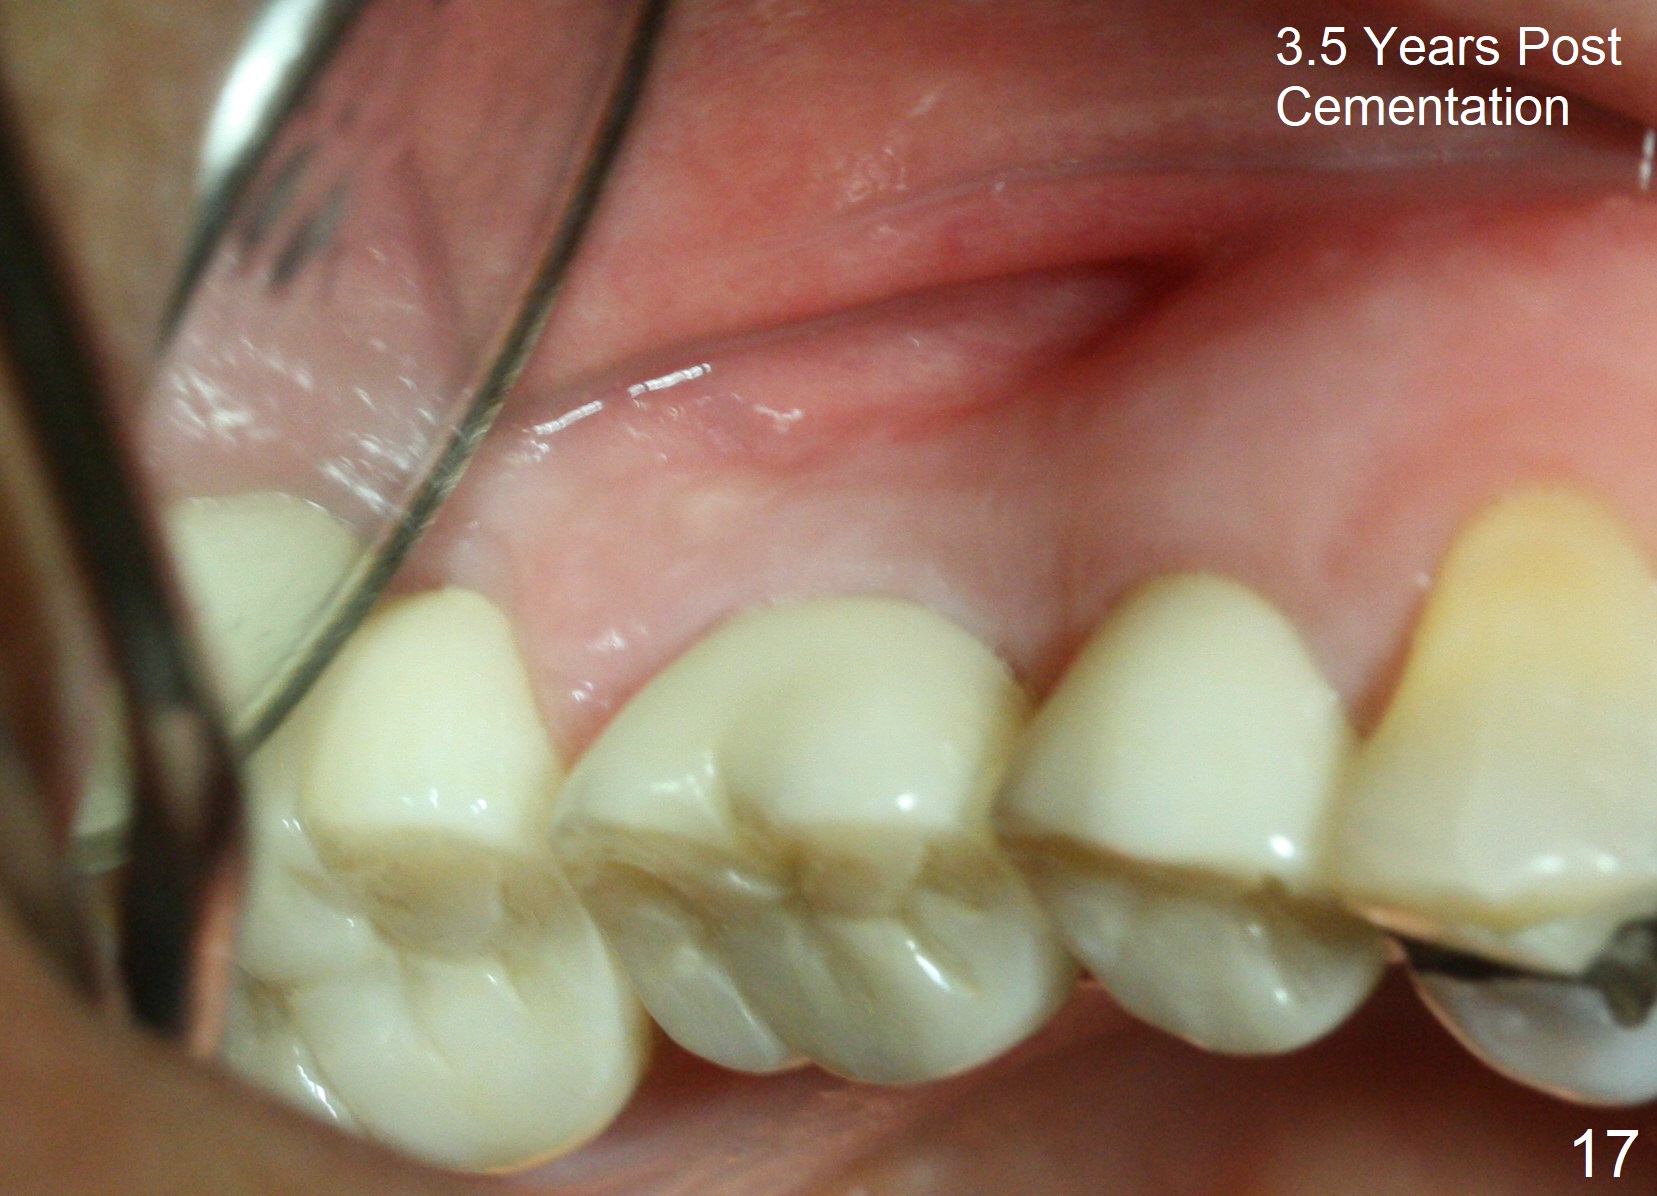

The bone density (Fig.1 white *) at the edentulous area (#3) is lower than that at the dentulous one (black *, 50 year-old man). The buccal plate is also atrophic and concave (Fig.2,3 arrowheads). A series of bone expanders are used to form osteotomy (following 1.6 mm pilot drill) at the depth of 14 mm (Fig.3 E 3.0 mm in diameter). When the last expander (4.3 mm) is removed from the osteotomy, the buccal plate appears to have been moved buccally (Fig.5 arrowheads). A 5.3x14 mm submerged implant (Fig.6 I) is placed with insertion torque >35 Ncm. The buccal plate seems to improve following placement of an 8.2 mm healing abutment and suturing (Fig.7). No bone graft is used. The buccal plate remains normal 12 days postop (Fig.8). It is slightly concave 3 months postop (Fig.9) with minimal bone resorption at the crest (Fig.10 (H: healing abutment),11 (A: cemented abutment). Nine months post cementation (12 months postop), bone resorption at the crest remains minimal (Fig.12) while the buccal plate (Fig.13 *) at #3 remains strong. Bone loss appears not to get worse 22 months post cementation (Fig.14). Soft and hard tissues remain healthy around the implant crown 3 years (Fig.15) and 3.5 years (Fig.16,17) post cementation.

In brief, bone expanders or osteotomes can be used for bone expansion and condensation to improve primary stability of implant placement. No bone graft appears to be needed. The buccal concavity remains minimal 6 years post cementation (Fig.18). In fact he is a bruxer with torus palatinus (Fig.19). The bridge of #9-11 is loose because of subgingival fracture of the abutment of #11 for 2.5 years (Fig.20).